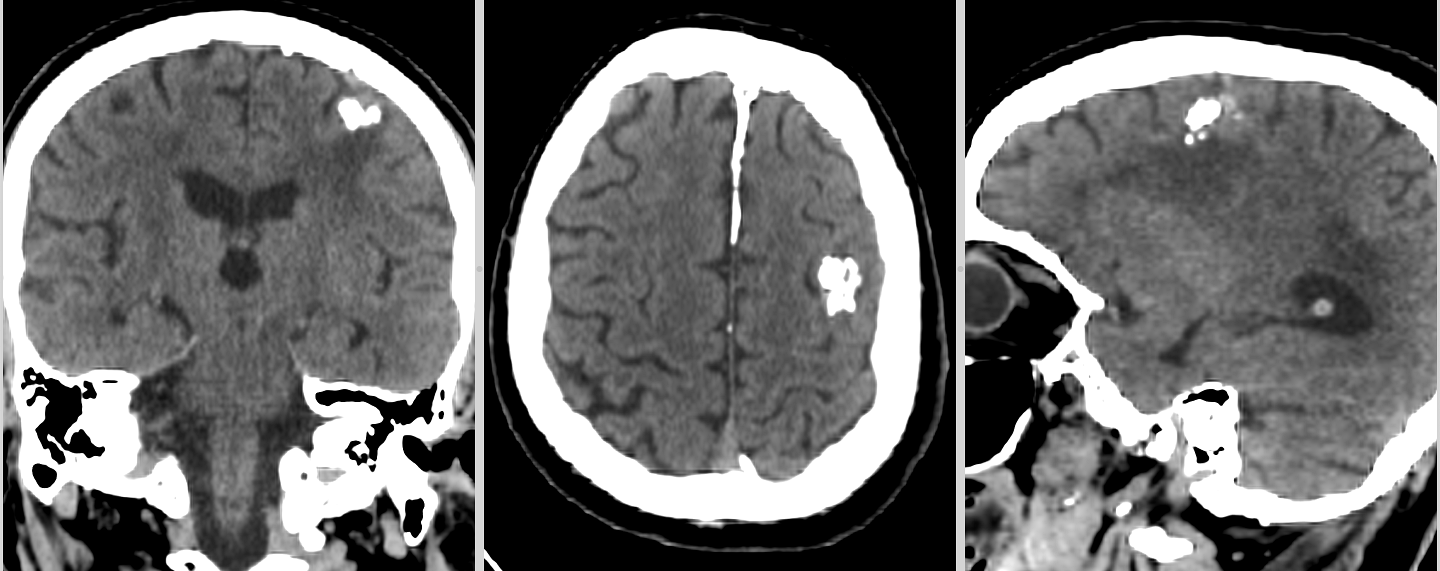

- Imagistică prin RMN: Aspecte caracteristice (leziuni corticale, fără edem semnificativ, fără contrast intens).

- Histopatologie: Prezența celulelor neuronale și gliale.

- Imunohistochimie: Markeri neuronali (NeuN, MAP2, synaptophysin) și gliali (GFAP).

- Teste moleculare: Căutarea mutațiilor BRAF, FGFR1, etc.